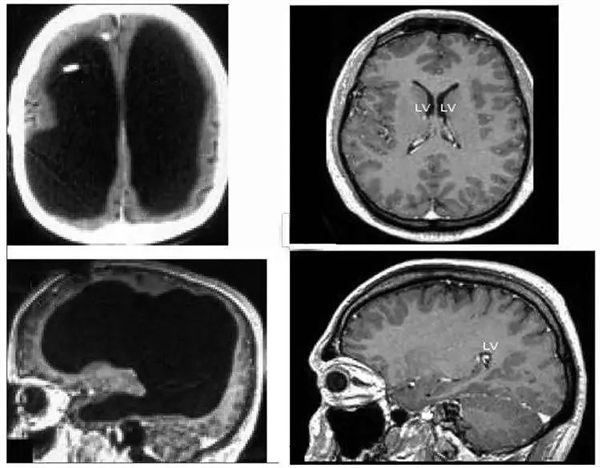

這位患者是法國人,前來就診時 44 歲,說自己左腿無力已經(jīng)兩星期了。這聽起來不是什么嚴重的大病,但詢問病史后醫(yī)生得知,他在 6 個月時患上了原因不明的腦積水,為此進行了引流,14 歲時又似乎因為引流引發(fā)過左腿的運動失調(diào)和輕度偏癱。大概是考慮到舊病復發(fā)的可能性,醫(yī)生對他進行了大腦 CT 和 MRI 掃描。Fqt驛資訊

掃描的結(jié)果令所有人大吃一驚。他的大腦中央是一灘巨大的積水,腦子被擠壓到了邊緣薄薄一層。當然嚴格來說這也不是純水,而是腦脊液。正常人腦子內(nèi)有少量的腦脊液,不斷產(chǎn)生又不斷排出到循環(huán)系統(tǒng)里,保持總量穩(wěn)定,但這位患者腦內(nèi)的排水系統(tǒng)發(fā)生了障礙,進多出少,導致液體越積越多。Fqt驛資訊

左邊為這名法國男子的大腦,中間黑色部分都是腦脊液;右邊為正常人的大腦Fqt驛資訊